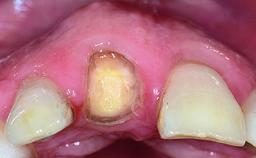

A healthy 37-year-old female patient was referred for a consultation on the replacement of missing tooth 21 with an implant-supported restoration. She stated that several years previously the tooth had been traumatically avulsed following a motor vehicle accident. The tooth was replaced with a three-unit fixed partial denture (FPD) immediately afterwards. Over time, she became disillusioned with the FPD and looked for a different option, including orthodontic therapy. She presented still in her orthodontic appliances, with the pontic sectioned free from the FPD but attached to the archwire. Her orthodontist felt that orthodontic treatment had been successfully completed, but nevertheless referred her before removing the appliances in case adjustments were necessary.

Bone Volume Horizontally and vertically sufficient Horizontally deficient Deficient vertically or deficient vertically AND horizontally

Bone Volume Deficient horizontally, allowing simultaneous augumentation